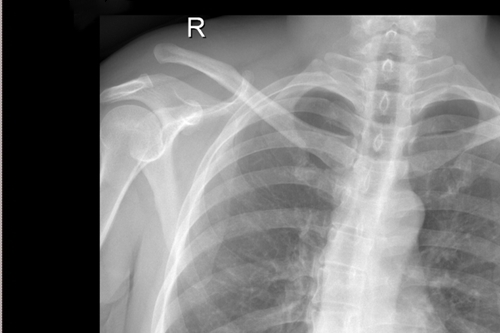

一名50岁的男性患者,因不慎摔伤致右肩关节肿痛,并伴活动受限4天后来附院求治。入院查体发现患者右肩部肿胀明显,右锁骨远端隆起畸形,局部明显按压出现疼痛,肩部外展活动受限,进行X线检查显示“右肩锁关节脱位”。骨三科医师团队根据患者病情,进行充分商讨,确定了手术治疗方案,决定为患者实施“右肩锁关脱位复位带袢钢板内固定术”。由副主任医师蒋宇平主刀,骨三科手术团队在患者锁骨上方及喙突处各取2cm手术切口,将肩锁关节复位后,使用瞄准器由喙突基底部向锁骨远端建立骨性隧道,最后将带袢钢板由骨道穿出后固定,术中出血仅10ml左右。

术前DR